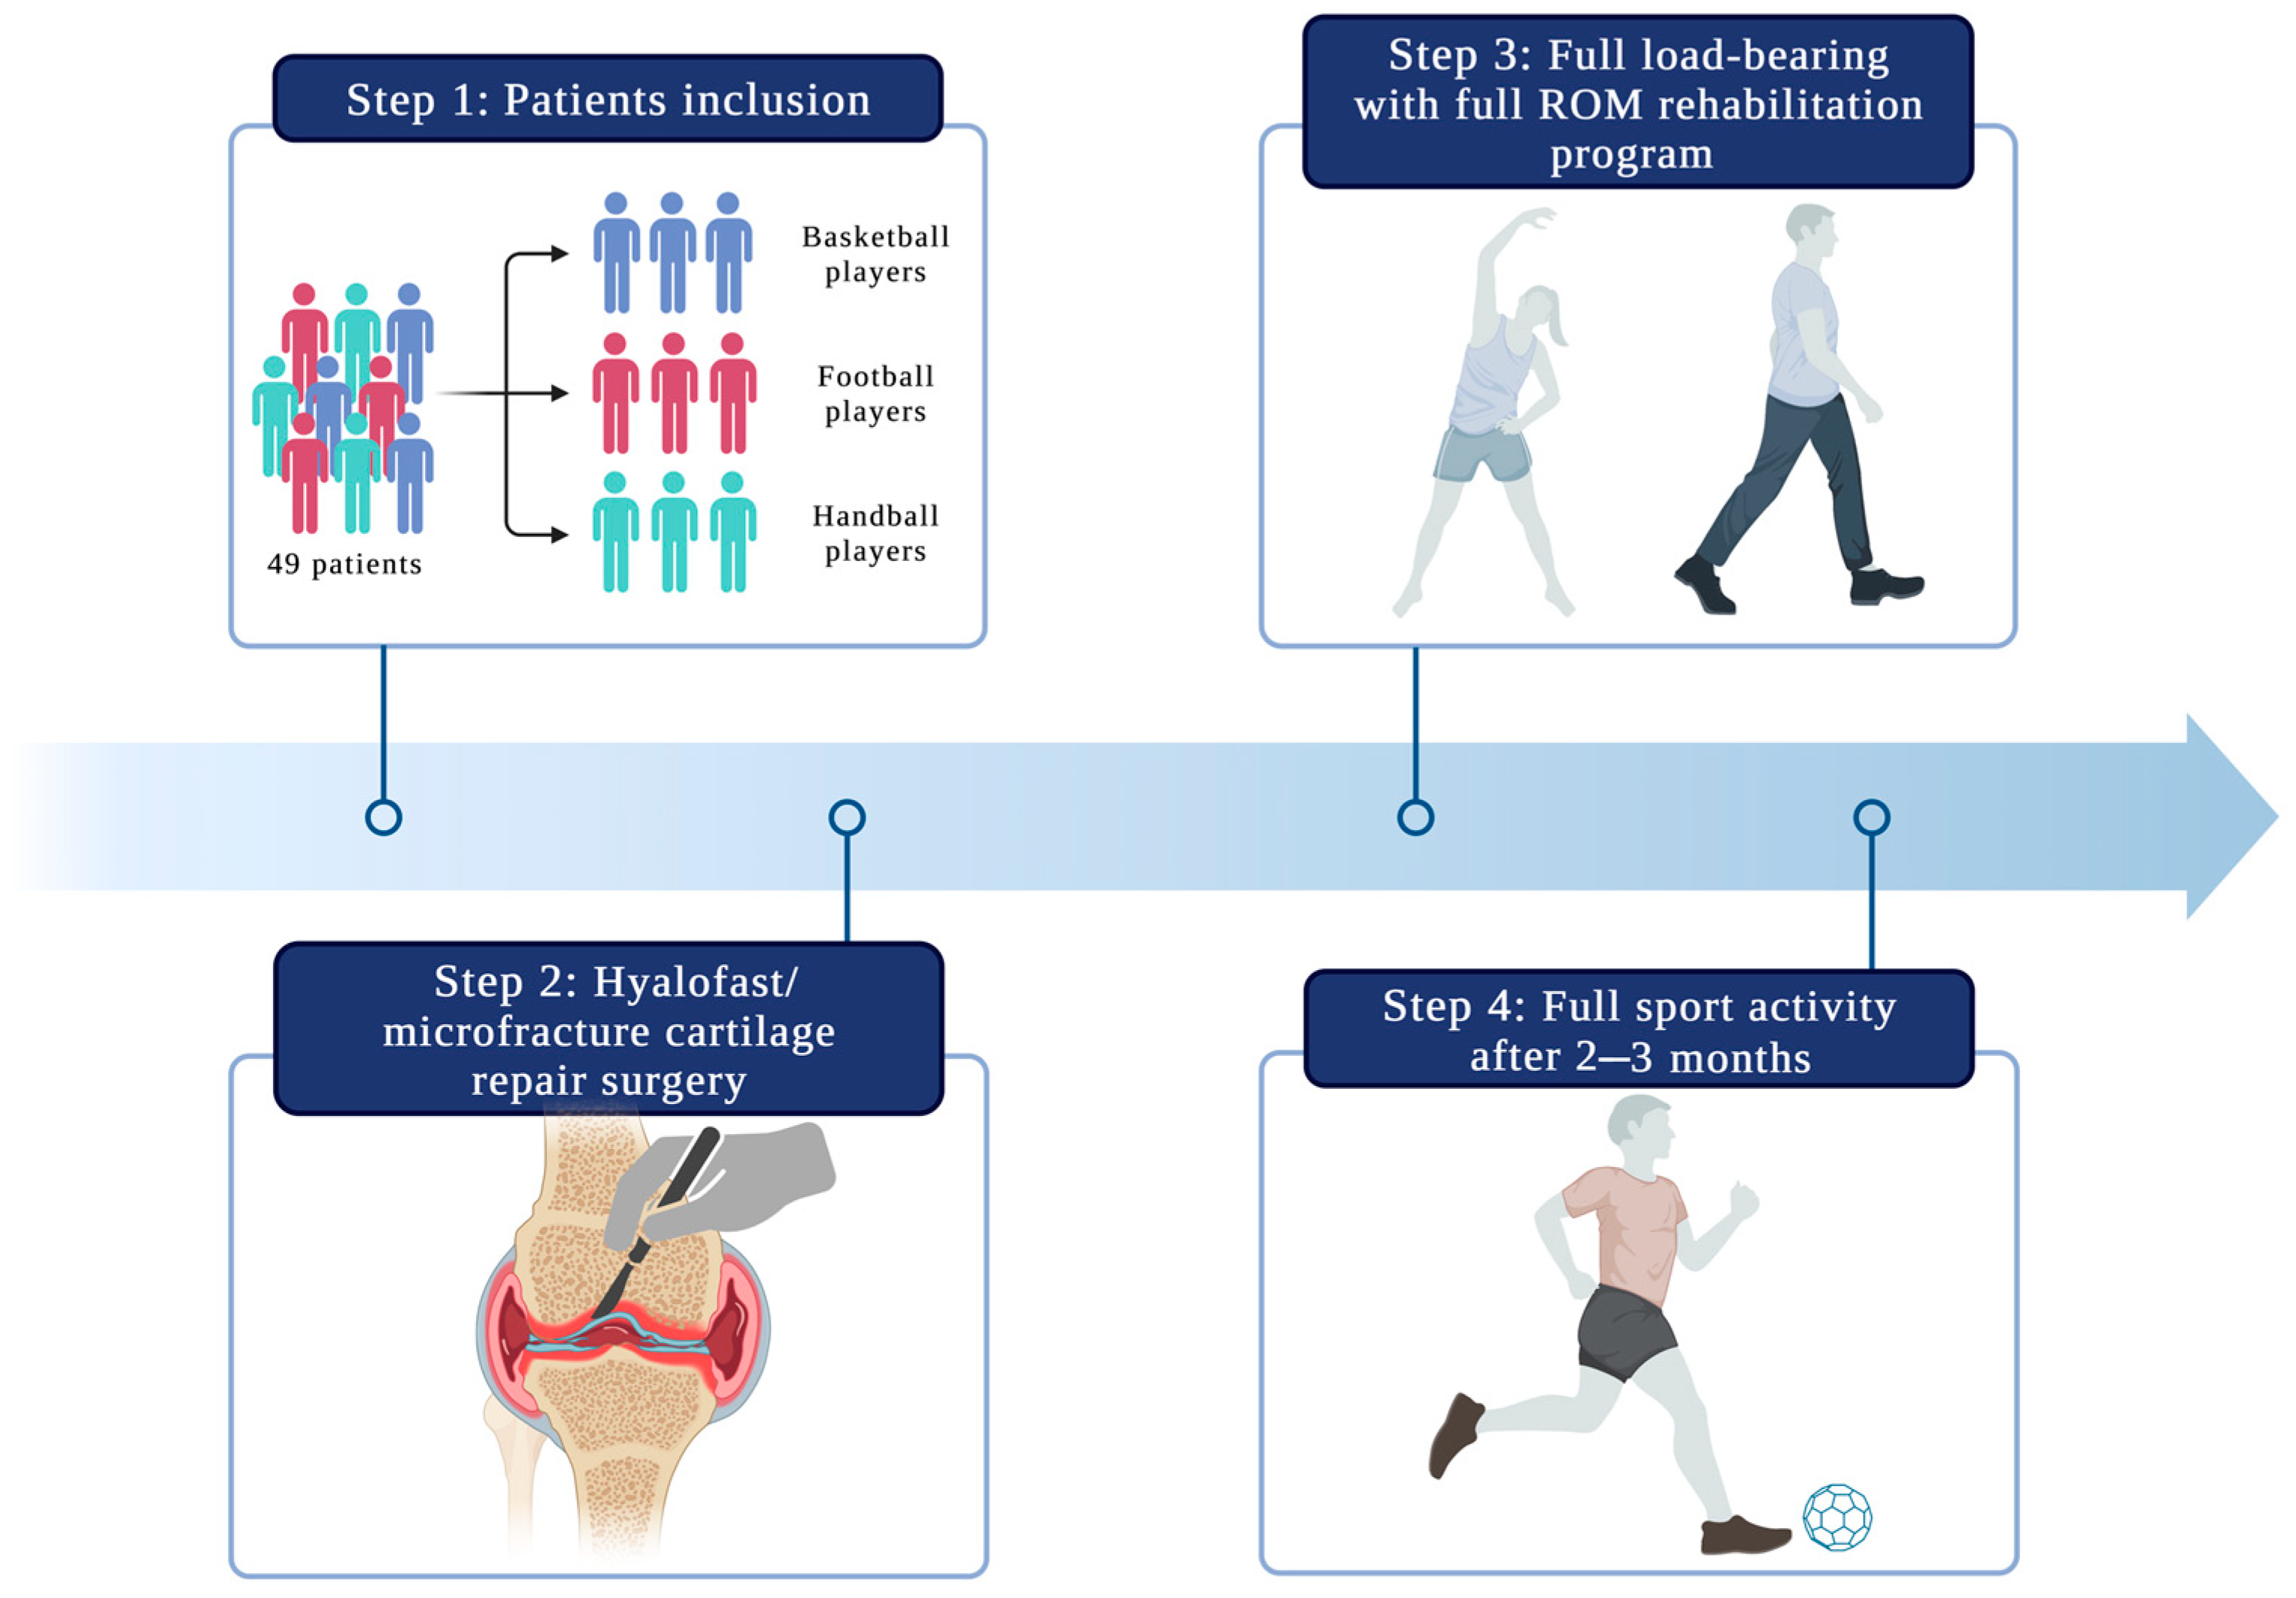

2. Materials and Methods

2.1. Patient Selection

2.2. Operation Procedure

2.4. Rehabilitation Protocol